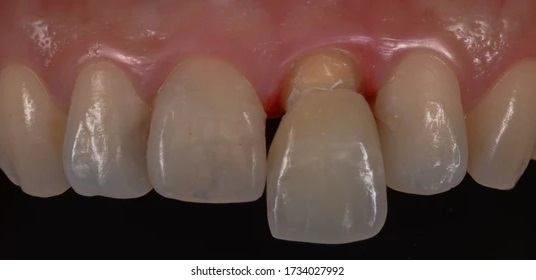

Bước 2: Đặt trụ lành thương cá nhân hóa để tạo hình mô nha chu.

Trụ lành thương cá nhân hóa sẽ được đặt luôn trong thì đặt trụ. Trong một số trường hợp xương hàm thiếu hổng hoặc lợi không đủ thể tích, Healing Customized có thể được đặt sau 2 tháng, sau khi trụ implant đã tích hợp.

trồng răng implant cá nhân hóa